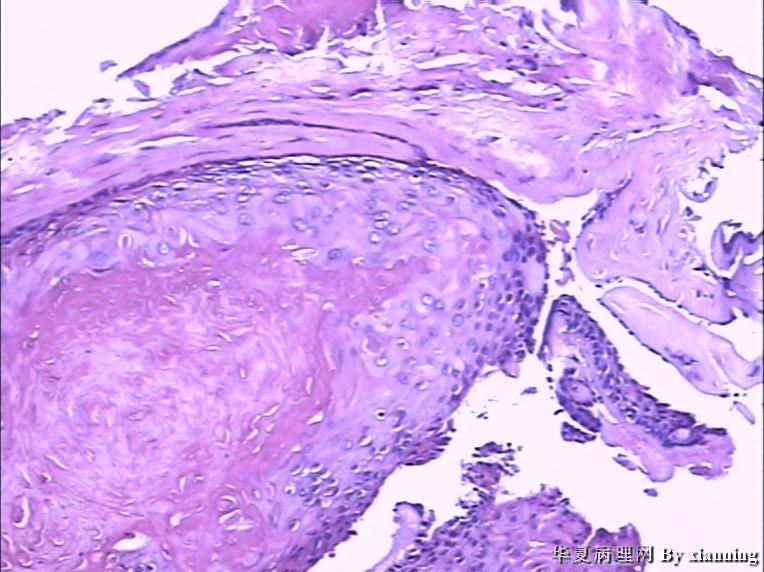

女 50岁 头皮下肿块

巨检:灰白色不规则结节0.9*0.7*0.4cm3,切面灰白色实性质地中等